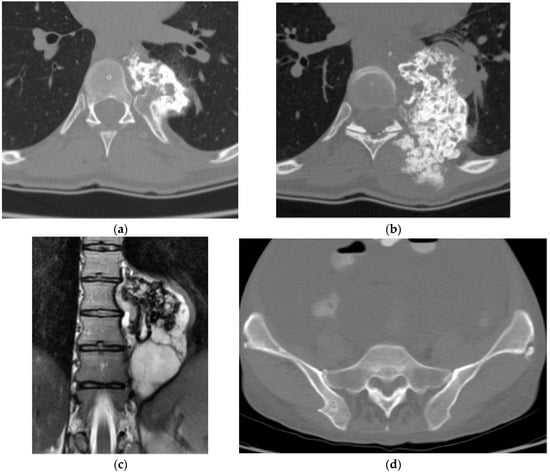

2.2.3. Chondrosarcoma